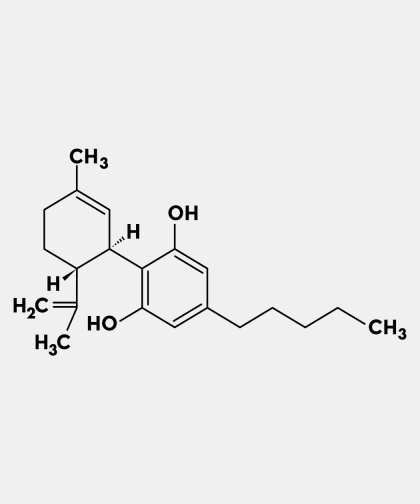

Ingredients: 100% Pure Dehydrated Sea MossBenefits:Rich Nutrient Profile: Contains vitamins, minerals, and amino acids.Digestive Health: Provides soluble fiber for regular bowelmovements.Thyroid Function: Iodine content supports healthy thyroid function.Joint and Connective Tissue Support.Immune System Support: Contains compounds with immune-modulating effects.Skin Health: Vitamins, minerals, and collagen may contribute tohealthy skin.Antioxidant Properties: Helps neutralize free radicals and supportscellular health.Energy Boost: Some users report increased energy levels.Drug Interactions: While sea moss is generally considered safe for most people, it’s essential to be aware of potential druginteractions, especially when combining them with chronic medications such as (but not limited to):Amiodarone, Antithyroid drugs.Sea moss contains iodine. Iodine can increase or decrease thyroid function.